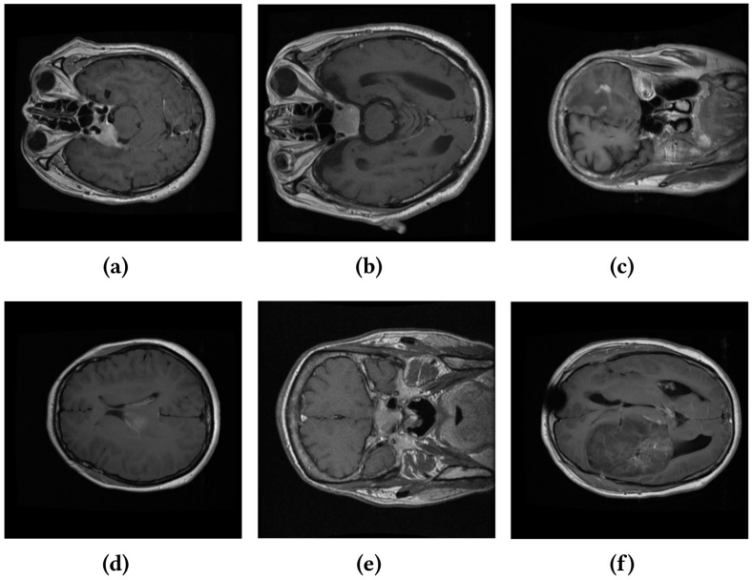

圖 1 醫學圖像中的類間相似性與類內差異性示例